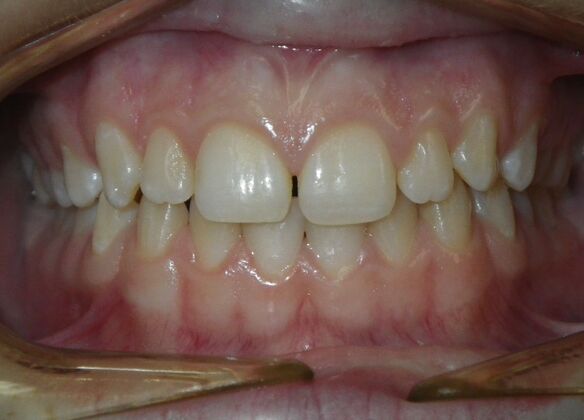

Patient presents desiring all spaces on upper and lower teeth closed. She will need slight expansion of upper arch due to lower molars leaning inward toward tongue. Used nitanium palatal expander with built in rotation of upper molars and lower lip bumper to upright lower first molars. Patient was also informed that her upper lateral incisors would require bonding due to their small size to close all space.